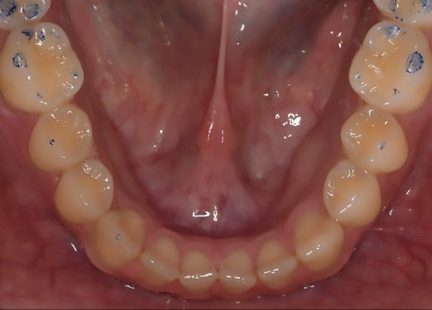

Classe III, béance, arcades étroites, arcades asymétriques, déviation médiane maxillaire, déviation médiane mandibulaire, décalage médian, encombrement, rotations, espacement, diastème

Mésialisation, courbe de Spee nivelée, égression, expansion, rétraction, vestibulo-version, fermeture de l'espace, traitement de phase II, élastiques : Classe III

- Arches alignées et coordonnées

- Forme de l'arcade améliorée

- Des arcades harmoniques ont été obtenues

- Expansion postérieure de l'arc supérieur.

- Mésialisation de l'arc supérieur (1-2 mm): Classe III molaire et canine à classe I molaire et canine.

- Incisive inférieure et couple de canine (facteur clé).

- Taquets d'égression optimisés au niveau des incisives supérieures et inférieures et des canines: fermeture à béance ouverte antérieure.

- Élastiques de classe III : Molaire et canine de classe III à molaire et canine de classe I. (Temps plein 22 heures/vêtements de jour).